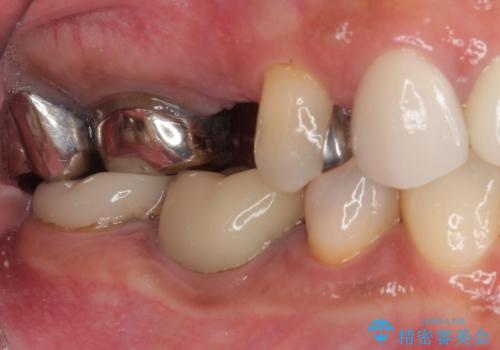

- 地元の歯科医院で治療を行っていたものの、難しいので都会に行くように指示をされたとのことで来院された患者様です。

右下のむし歯が歯肉縁下に及んでおり、歯周外科処置(歯冠長延長術)を行った上で、根管治療を行い、状態を整えて補綴治療を行うこととしました。